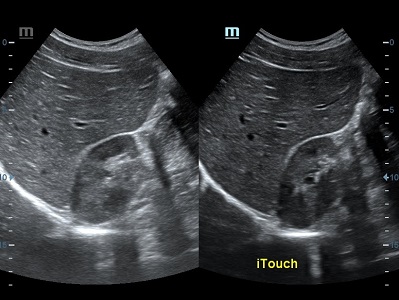

Оптимизация изображения происходит и за счет постобработки. Наиболее часто используемый инструмент - общее усиление (Gain). Усиление делает изображение «ярче», но чем сильнее усиление, тем меньше различия между структурами. Также используются усиление по времени (TGC) и усиление по длине (LGC), которые позволяют изменять отображение на экране послойно, позволяя подсветить гипоэхогенные участки, или, наоборот, снизить визуально эхогенность слишком ярких моментов. Данный вид оптимизации требует много времени, для упрощения работы доктора на приборах Mindray внедрена система автоматической оптимизации - iTouch.